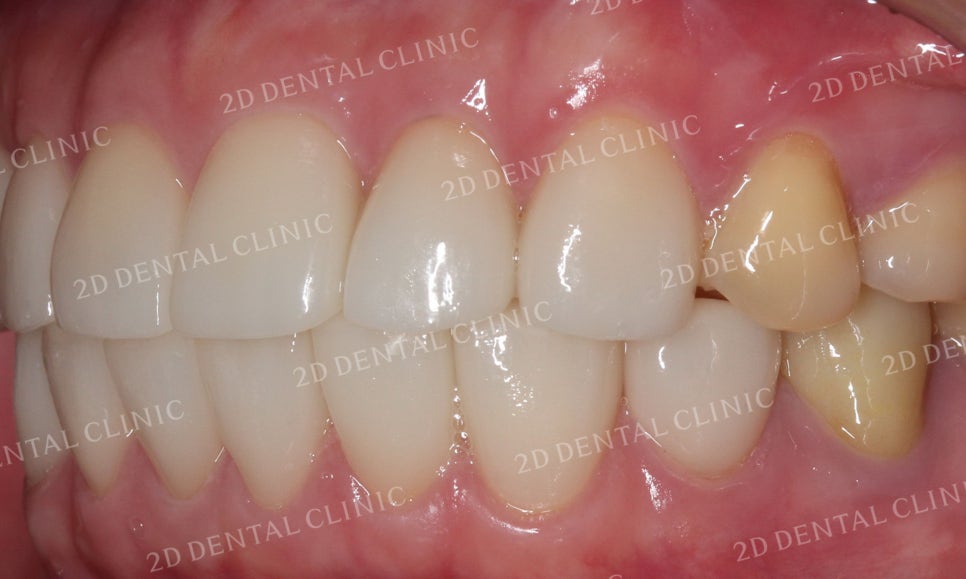

블링스 시술 전 후

안모의 자세한 사진에서도

비어있던 빈 틈이 완벽하게 채워진 모습입니다.

블랙트라이앵글이 보이던 하악도

잘 채워진 모습이네요!